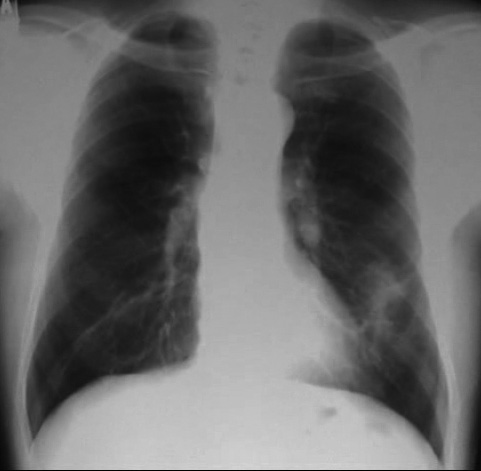

• X線検査では,通常,両肺の中・下部領域に多数の空洞化した転移性結節が認められる. 肺外への浸潤は極めて稀. 皮膚,中枢神経系,肝臓,腎臓などにも転移が見られる.

今月定期受診で1年ぶりにchest X-pを撮影. 両肺野に多発結節影が指摘されて受診となった.

chestX-pとCT.サムネイル画像クリックで大きな画像がみられます.